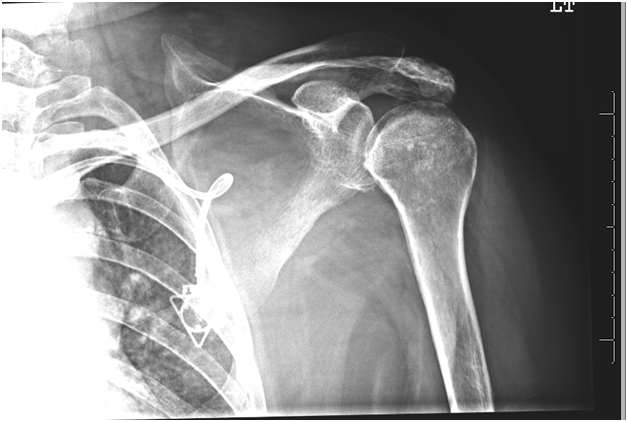

Radiographs revealed osteonecrosis of both humeral heads (Figure 1 & 2) with subchondral collapse bilaterally and mild arthrosis of the left glenohumeral joint. She had seen several orthopaedic surgeons regarding her severely disabling shoulder pain. It was determined that due to progressive CNS metastatic disease and recent hospitalization for gastrointestinal bleeding requiring transfusion that this patient was at unacceptably high risk for an arthroplasty procedure. Non operative therapy, including multiple opiate based pain medications, had failed to improve her quality of life so a less risky treatment was sought.

Figure 2 AP radiograph of the left shoulder showing sclerosis and subchondral collapse of the humeral head, and no degenerative changes of the glenoid.